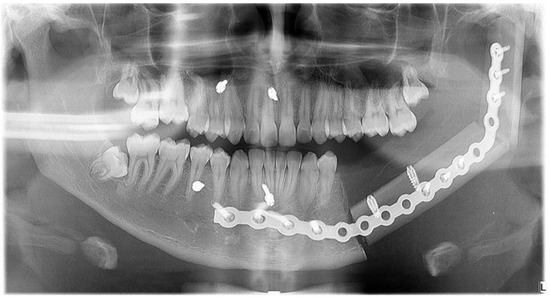

2.2. Case 2